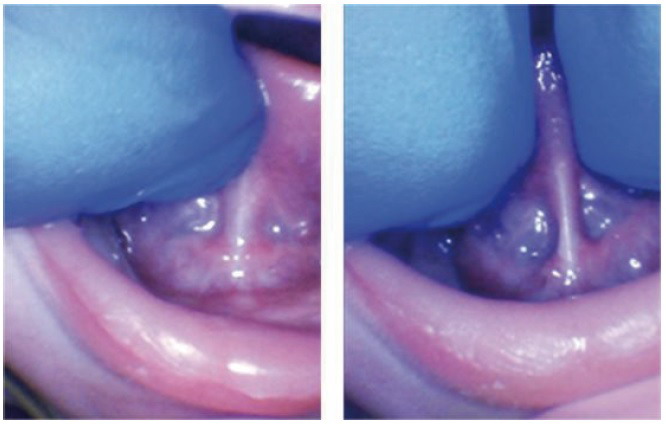

婴儿后舌系带:舌抬高和两指评估显示粗的、限制性的舌系带。